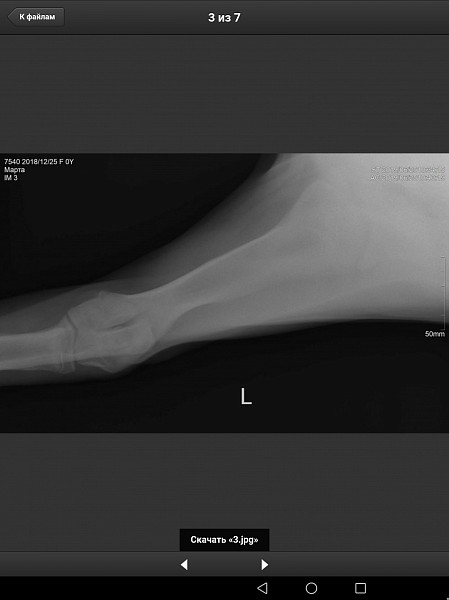

У нас немецкий дог, девочка, 6 месяцев, привита по возрасту. Поставлен диагноз Расслаивающий остеохондрит плечевого сустава (мышь плечевого сустава). Сказали, нужна операция по зачищению этого сустава. Как можно скорее.

Есть рентгеновский снимок. Прошу вас прокомментировать его, правильный ли диагноз? Как срочно нужно оперировать, если подтвердится диагноз? Какой период реабилитации? И, что нас ожидает в будущем, от чего могла развиться болезнь, наследственное это или нет, что делать, чтобы предупредить заболевание суставов других лап?

Здравствуйте. Судя по описываемым вами симптомам у собаки, действительно имеется поражения хрящевой поверхности какого-то сустава грудой конечности. На предоставленных вами снимках, затруднительно тщательно рассмотреть суставные поверхности. Ярко выраженной патологии хряща (расслаивающий остеохондрит не просматривается). Для подтверждения или исключения данной патологии наиболее оптимальным является компьютерная томография. При подтвтерждении диагноза, основным методом лечения является хирургическое вмешательство, направленное на устранение фрагментированного участка хряща и зачищении дефекта для формирования на месте поражения волокнистого хряща.